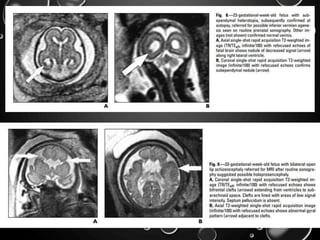

VENTRICULOMEGALY

• MOST COMMON; SONOGRAPHY. - ATRIAL WIDTH GREATER THAN 10

MM MEASURED AT THE POSTERIOR MARGIN OF THE GLOMUS OF THE

CHOROID PLEXUS ON AN AXIAL PLANE THROUGH THE THALAMI .

• DESPITE THE GROWTH OF THE SURROUNDING BRAIN, THE ATRIAL

DIAMETER IS RELATIVELY CONSTANT FROM 15 TO 35 WEEKS

’GESTATION, SO THE LATERAL VENTRICLES APPEAR

PROPORTIONATELY LARGER EARLY IN GESTATION .

• ASSOCIATED STRUCTURAL ABNORMALITIES INCLUDE NEURAL TUBE

DEFECTS, AGENESIS OF THE CORPUS CALLOSUM, DANDY-WALKER

SYNDROME, HOLOPROSENCEPHALY, CORTICAL MALFORMATIONS,

INTRACRANIAL HEMORRHAGE, AND PORENCEPHALY

• INCLUDING AGENESIS OF THE CORPUS CALLOSUM,

CORTICAL MALFORMATIONS, PERIVENTRICULAR

HETEROTOPIA, PERIVENTRICULAR LEUKOMALACIA,

MULTICYSTIC ENCEPHALOMALACIA, AND INTRACRANIAL

HEMORRHAGE.

• PERIVENTRICULAR WHITE MATTER INJURY MAY MANIFEST

AS FOCAL PERIVENTRICULAR T2 HYPERINTENSITY, FOCAL

DEFECTS IN THE GERMINAL MATRIX, SUBTLE IRREGULARITY

OF THE VENTRICULAR MARGIN, OR LARGE AREAS OF

ABNORMAL SIGNAL IN THE DEVELOPING WHITE MATTER

AND OVERLYING CORTEX. MAY OR MAY NOT BE

ASSOCIATED WITH VOLUME LOSS.

• HEMORRHAGE IS USUALLY DETECTED AS FOCI OF

T1HYPERINTENSITY AND T2 HYPOINTENSITY IN THE

GERMINAL MATRIX, VENTRICLES, OR BRAIN PARENCHYMA.

• BLOOD IN THE VENTRICLES MAY LAYER OR FORM A

DISCRETE CLOT.